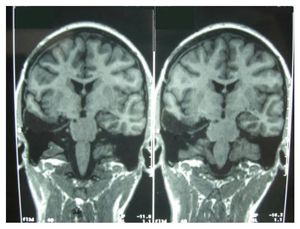

A woman suffering from a particular kind of epilepsy, had to get her amygdala removed. That is a particular part of the brain which is responsible for generating emotions. While you would expect someone with their amygdala removed to be less empathetic towards others, this woman apparently suffered from 'hyper empathy'. Doctors then tested her physiological reactions and asserted that despite the amygdala being removed, the other parts of the brain formed new connections which, in a way, boosted her empathy skills. You would say surgery for epilepsy? Yes Epilepsy surgery is performed to either remove the brain area where seizures begin or stop the spread of seizure activity. It is a treatment option for people with seizures that are not controlled with medication. "Medically intractable seizures" are defined as persistent seizures despite trials of three or more antiepileptic drugs, alone or in combination. The goal of surgery is to to achieve better seizure control without causing loss of brain function. Surgical results can be considered curative (stopping the seizures) or palliative (restricting the spread of the seizure). The type of surgery performed depends on the type of seizures and where they begin in the brain . Curative procedures, such as lobectomy, cortical excision, or hemispherectomy aim to remove the area of the brain (seizure focus) causing seizures.